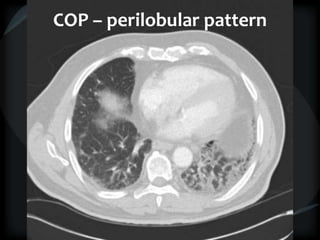

Airspace Patterns

 Perilobular pattern

COP – perilobular pattern